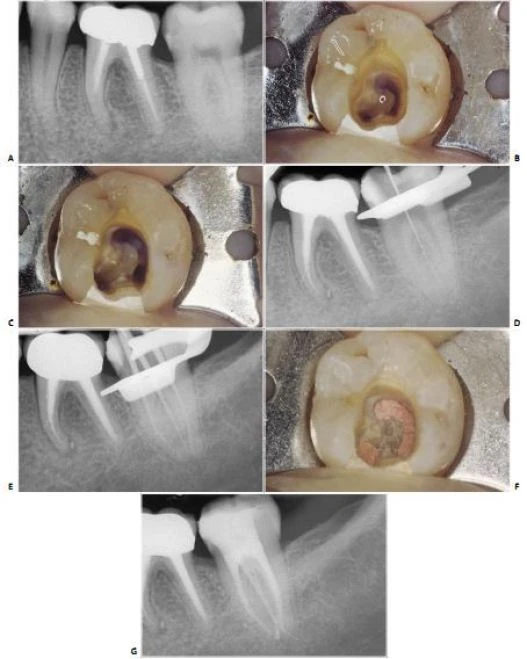

Thay vì có ba miệng ống tủy riêng biệt, ba ống tủy có hình dạng một chữ C, phần cong đối diện với phía ngoài (hình 11.131).

Đưa dụng cụ vào phần ngoài gần cho một hình ảnh X-quang không bình thường, dẫn đến nghi rằng đã bị thủng sàn, thật vậy, thật vậy, nó là ống tủy ngoài gần và ống này có thể thông nối với ống tủy xa (hình 11.132) hoặc ống tủy gần trong (hình 11.133). Ống tủy hình C do miệng các ống tủy khác nhau nối lại với nhau và sự nối thông này có thể mở rộng về phía chóp đến những độ sâu khác nhau, và điều này có thể quan sát được chỉ bằng việc trám ống tủy chân răng (hình 11.134 – 11.136).

Hình 11.131. Một răng cối lớn thứ hai hàm dưới với ống tủy hình chữ C. A. Phim trước điều trị. B. Xoang tủy. Lưu ý rằng hình ảnh chữ C điển hình là do sự nối nhau giữa ba miệng ống tủy. C. Trám bít theo ba chiều không gian bằng côn gutta percha. D. Phim sau điều trị. Sự thông nhau hình chữ C kéo dài đến vị trí 1/3 chóp.

Hình 11.132. Răng cối lớn thứ hai hàm dưới với ống tủy hình chữ C, trong đó ống tủy gần ngoài chạy vào ống tủy xa. A. Phim trước điều trị. B. Một dụng cụ được đưa vào chỗ lồi của chữ “C” giống như hình ảnh thủng sàn; thật vậy, ống tủy gần ngoài trong trường hợp này được dự đoán chạy vào trong ống tủy xa. C. Phim sau điều trị. D. Sau ba năm.

Hình 11.133. Răng cối lớn thứ hai hàm dưới bên trái với một ống tủy hình chữ C, trong đó ống tủy gần ngoài chạy vào trong ống tủy gần trong. A. Phim trước điều trị không phát hiện được sự hiện diện của một ống tủy hình chữ C. B. Phim trong lúc điều trị: một dụng cụ đưa vào chỗ lồi của chữ C giống như hình ảnh thủng sàn; thực ra, ống tủy gần ngoài trong trường hợp này chạy vào trong ống tủy gần trong. C. Phim trong lúc điều trị khi lèn ở vùng chóp: chỉ bằng kỹ thuật lèn với gutta percha nóng chảy mới có thể trám kín được ống tủy hình chữ C theo ba chiều không gian. D. Sau ba năm.

Hình 11.134. Răng cối lớn thứ hai hàm dưới với một ống tủy hình chữ C. Sự giao nhau giữa ba ống tủy tạo nên hình dải băng kéo dài về phía chóp đến 1/3 giữa. A. Phim trước điều trị. B. Xoang tủy với miệng ống tủy hình dải băng điển hình. C. Phim sau điều trị. D. Phim sau 18 tháng.

Hình 11.135. Răng cối lớn thứ hai hàm dưới với một ống tủy hình chữ C không hoàn toàn. A. Phim trước điều trị. B. Xoang tủy: hình ảnh ba ống tủy nối nhau bởi một rãnh với góc lồi về phía ngoài. Một ống tủy hình chữ C được chẩn đoán. C. Sau khi hoàn thành việc làm sạch và tạo hình, hình ảnh chữ C không hoàn toàn, vì nó chỉ liên quan đến ống tủy xa và ống gần ngoài. D. Một dụng cụ được đưa vào ống tủy gần ngoài cho thấy sự giao nhau giữa ống tủy này với ống tủy gần trong. E. Phim sau điều trị.

Hình 11.136. Răng cối lớn thứ hai hàm dưới với ống tủy hình chữ C không hoàn toàn. A. Phim trước điều trị. B. Xoang tủy. Hình ảnh ống tủy xa và ống tủy gần ngoài giao nhau bởi một rãnh với góc lồi về phía ngoài. C. Xoang tủy khi sửa soạn ống tủy. D. Một dụng cụ được đưa vào ống tủy ngoài gần, nghi ngờ có sự giao nhau giữa ống này với ống tủy xa. E. Phim trong miệng khi thử côn. F. Xoang tủy sau khi quá trình trám bít ống tủy hoàn thành. Ống tủy có dạng hình chữ C không hoàn toàn. G. Phim sau điều trị. Lưu ý rằng ống tủy ngoài gần giao với ống tủy xa nhưng không nhập vào ống tủy xa mà lại có một lỗ chóp riêng biệt.